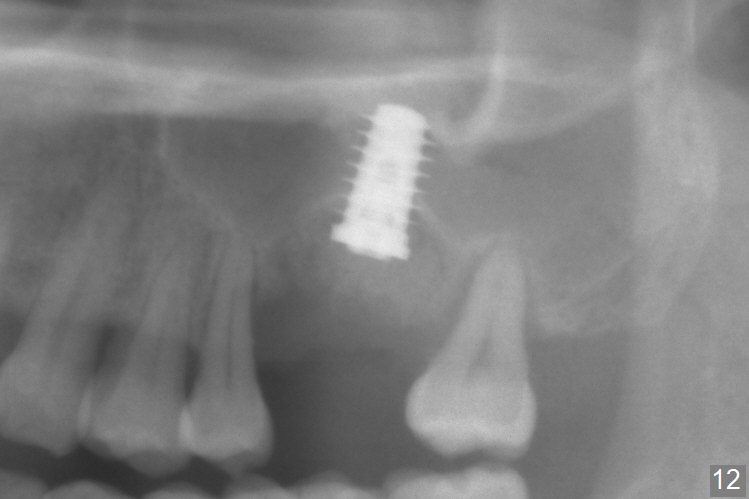

When the displaced tooth #14 (Fig.1) with palatal gingival recession (Fig.2) is extracted, the buccal plate is low, while the palatal one is lost.  Osteotomy is initiated in the bottom of the large socket with Marking Drill.  The bone turns bluish, suggesting thin bone (in fact less than 1 mm as well as low density).  Magic Sinus Lifter (Fig.3 *, Fig.4 blue area) is used for sinus lift (Fig.4 (red curved line: lifted sinus membrane; grey area: a portion of the lifted sinus floor), followed by insertion of a piece of PRF plug and Vanilla bone graft for sinus lift.  The osteotomy is enlarged lightly with 4.8 mm Magic Drill (compare black strips between Fig.4,5).  A 5x9 mm dummy implant (Fig.5 green) is dislodged into the sinus.  The lifted sinus membrane holds the implant in place.  The black thin strip in Fig.5 and black circle in Fig.6a (occlusal view) represents the osteotomy.  After increase in the osteotomy with Lindamann bur (Fig.6b red circle), the implant (Fig.6c green) is retrieved with endodontic forceps (Fig.6c two blue dots (beaks of the forceps); Fig.7,8).  With the enlarged osteotomy (Fig.6d), a 6x9 mm dummy implant is placed deep (Fig.9).  The definitive implant is 6.5x11 mm with insertion torque ~ 15 Ncm (Fig.10).  With placement of a healing screw and further placement of allograft (Fig.11 *), the socket is closed with PRF membrane and collagen plug (Fig.12).